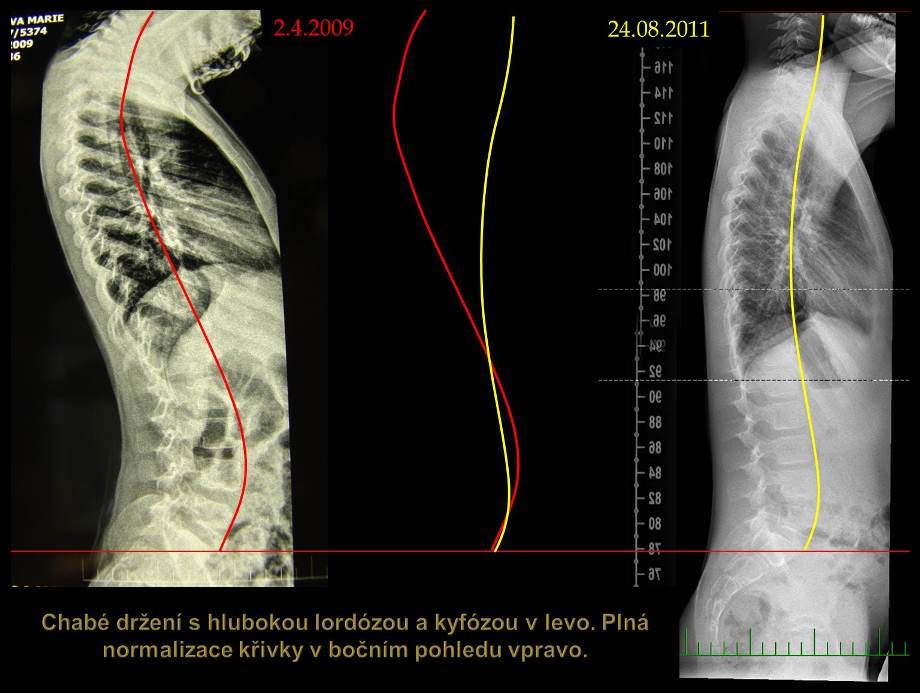

Skoliózu môžeme charakterizovať ako trojrozmernú deformitu so sklonom a posunom stavcov vo frontálnej (stranové zakrivenie), sagitálnej (zmeny fyziologickej lordózy a kyfózy) a tranzverzálnej (rotácia chrbticového stĺpca) rovine. Jednoducho povedané, je to chorobné vykrivenie chrbtice mimo jej prirodzenú krivku.

Veľkosť deformity sa hodnotí vo všetkých troch rovinách. Metódou podľa Cobba možno odčítať uhlovej zakrivenie v predozadnej projekcii (AP = Antero-posterior) a v bočnej projekcii (sagitálnej rovine). Modernými zobrazovacími metódami možno navyše v osovom reze trupu (v transversálnej rovine) odčítať rotáciu chrbtice.